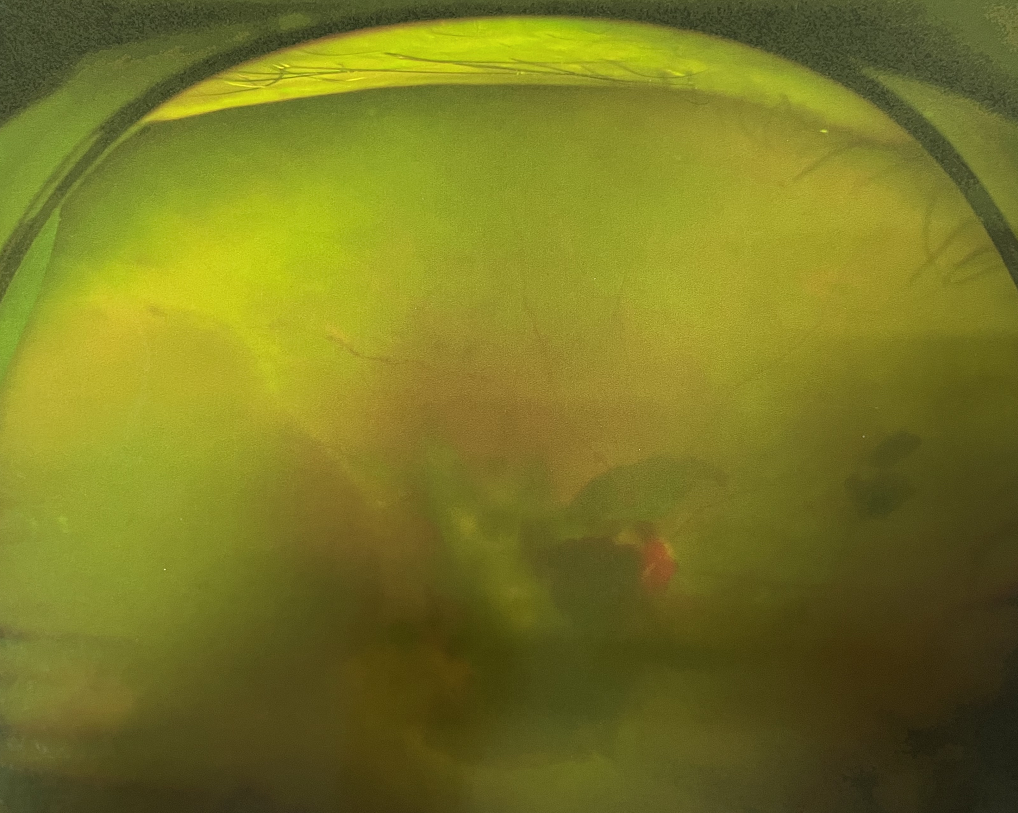

四十多歲的王女士,患高血壓病及Ⅱ型糖尿病多年,一直靠藥物控制血壓和血糖。去年,王女士右眼看手機(jī)時(shí)感覺視物不清,總感覺眼前有一層霧,視力也逐漸下降,于是來(lái)廈門大學(xué)附屬?gòu)B門眼科中心就診。

眼底病??茝埿』⑨t(yī)生檢查后,診斷王女士為“雙眼玻璃體積血、雙眼糖尿病視網(wǎng)膜病變V期”。(V期即5期,纖維增生期,出現(xiàn)纖維膜,可伴視網(wǎng)膜前出血或玻璃體出血。)

張小虎醫(yī)生為王女士進(jìn)行右眼玻璃體腔注藥術(shù),3天后進(jìn)行右眼23G玻璃體切割術(shù)后視力有所提升。

4個(gè)月后王女士來(lái)院取硅油,取油后視力恢復(fù)到0.6。“當(dāng)時(shí)來(lái)的時(shí)候真的只能看到模糊的影子,特別害怕覺得完了,想說(shuō)眼睛估計(jì)要瞎了,沒想到手術(shù)后視力竟然提升了,現(xiàn)在也看得比較清楚了。”王女士說(shuō)到。

張小虎醫(yī)生表示,糖網(wǎng)病進(jìn)展到嚴(yán)重增殖期帶來(lái)的視力損傷往往是極其嚴(yán)重的,目前王女士右眼從術(shù)前0.02恢復(fù)到術(shù)后0.6,已屬十分難得。

右眼術(shù)前